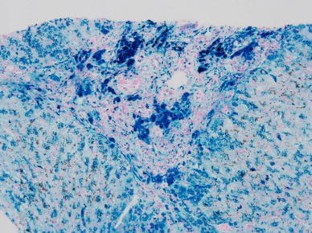

Reticuloendothelial iron overload is associated with secondary hemochromatosis including repeated transfusions and iron over-supplementation. Ferroportin disease B is a severe subtype of hereditary iron overload syndrome with an activated reticuloendothelial system. The iron exporter ferroportin may be insensitive to hepcidin 25 in this subtype. However, the interactions between the hepcidin–ferroportin system and modifiers of reticuloendothelial iron overload have not yet been elucidated. We describe two patients with iron overload conditions that were compatible with ferroportin disease B, but their genetic backgrounds and habitual states differed. Both patients had diabetes, periportal fibrosis with severe iron deposits in their hepatocytes and Kupffer cells, and adequate levels of circulating hepcidin 25. However, the first patient was heterozygous for a mutation in the FP gene and free from the acquired factors of iron overload, while the second patient was a heavy drinker with a heterozygous mutation in the TFR2 gene and no mutations in the FP gene. The first patient was the second reported case of ferroportin disease B in Japan. Our study on these 2 patients suggests that liver fibrosis associated with compound iron overload of reticuloendothelial cells and hepatocytes may occur via multi-etiological backgrounds.

Fig. 1